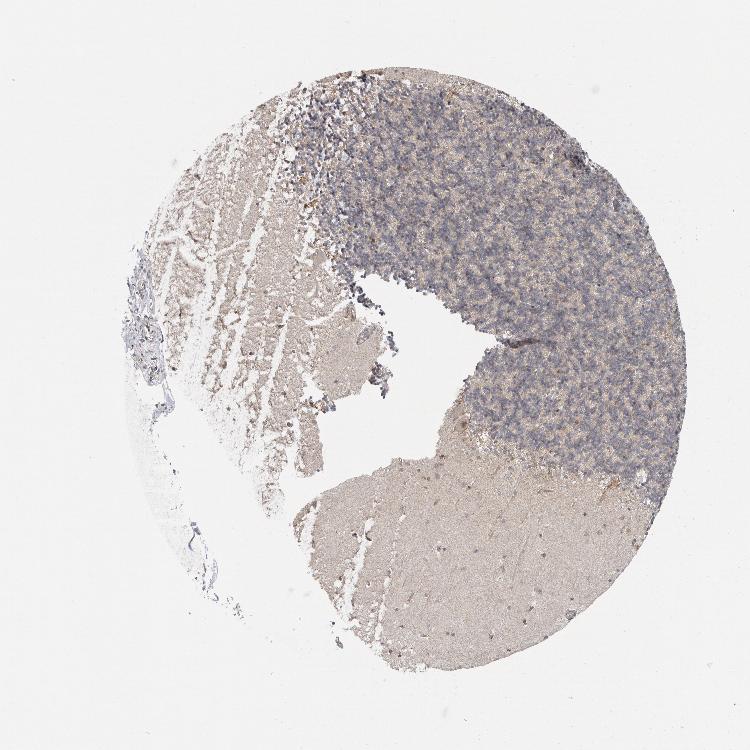

CEREBELLUM - Antibody stainingi

Antibody staining in the annotated cell types in the current human tissue is reported as not detected, low, medium, or high, based on conventional immunohistochemistry profiling in selected tissues. This score is based on the combination of the staining intensity and fraction of stained cells.

Each image is clickable and will lead to virtual microscopy that enables deeper exploration of all samples and also displays staining intensity scores, fraction scores and subcellular localization as well as patient and tissue information for each sample.

Antibody HPA023609Antibody HPA024619Antibody HPA025717

Purkinje cells Not detectedHighLow

Cells in granular layer Not detectedLowNot detected

Cells in molecular layer Not detectedLowMedium